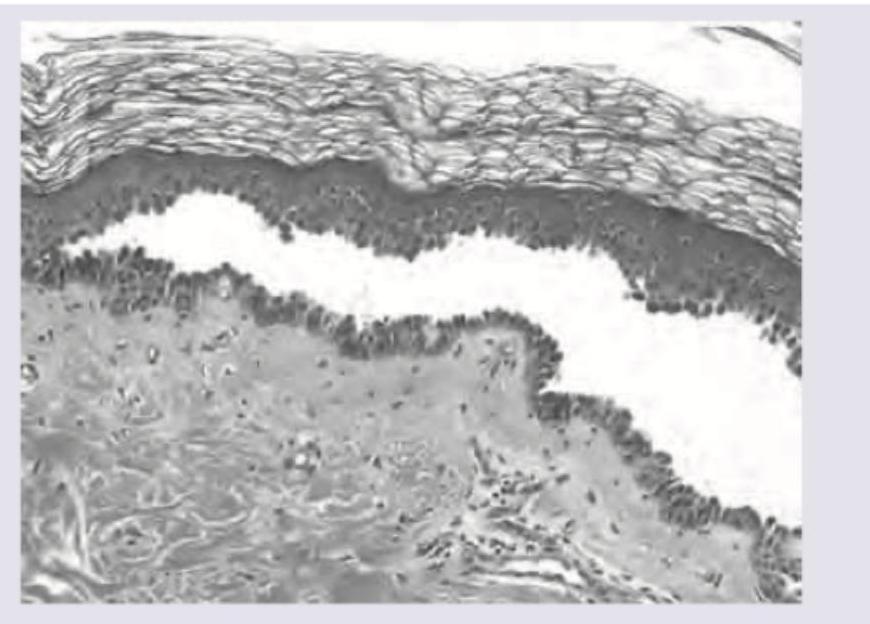

The morphological pattern of inflammation shown here is:

Explanation: ***Serous*** - Characterized by **watery, protein-poor fluid** with minimal cellular content, typically seen in **blisters** and **vesicles**. - Classic example includes **skin blisters** from burns or allergic reactions, where clear fluid accumulates in tissue spaces. *Fibrinous* - Features **fibrin strands** and **fibrin deposits** creating a mesh-like appearance on tissue surfaces. - Commonly seen in **pericarditis** and **pleuritis**, where fibrin forms a "bread-and-butter" appearance on organ surfaces. *Purulent* - Contains abundant **neutrophils** and **pus formation** with thick, yellowish inflammatory exudate. - Typical of **bacterial infections** like abscesses, where neutrophil infiltration dominates the inflammatory response. *Chronic* - Dominated by **lymphocytes**, **macrophages**, and **plasma cells** rather than acute inflammatory cells. - Develops over **weeks to months** and often involves **tissue destruction** and **fibrosis** formation.